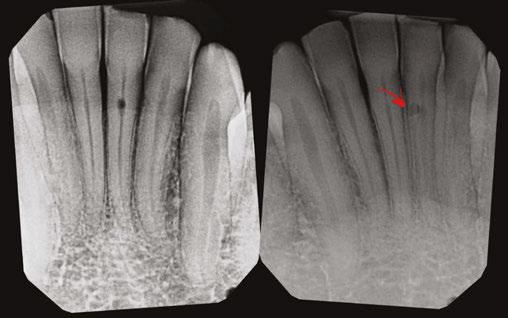

A 56-year-old male presented with a chief complaint of vague discomfort in the left mandible. The patient reported that the discomfort had been intermittent for more than 6 months but

Figures 4A-4H: 4A. Preoperative periapical radiograph of tooth No. 19. Visualization of periapical radiolucency associated with mesial root is possible. Root also appears to be calcified in middle and apical thirds. 4B. Sagittal CBCT slice showing internal resorption in apical portion of mesial root. Visualization of resorptive defect perforating on distal aspect of mesial root, and significant periapical pathology extending close to furcation is possible. Defect and extent of pathology was not visualized on periapical radiograph. 4C. Axial CBCT slice showing resorptive defect encapsulating both MB and ML canals and perforating on distal aspect of mesial root. There is significant bone loss adjacent to perforating defect. 4D. Coronal CBCT slice showing internal resorptive defect encapsulating both mesiobuccal and mesiolingual canals. 4E. Immediate postop radiograph after completion of endodontic treatment. 4F,4G. Coronal and axial CBCT slice at 16-month follow-up. Note resorptive defect filled with bioceramic sealer and complete healing of adjacent bone and reestablishment of PDL. Patient returned at 16-month point for endodontic treatment of tooth No.18. 4H. Three-year follow-up radiograph. Patient remained completely asymptomatic on tooth No 19

had recently worsened. Clinical examination revealed pain to percussion on tooth No. 19. No swelling was observed, and the tooth was not sensitive to palpation or biting. Radiographic and CBCT (Veraviewepocs 3D R100; J. Morita) examination revealed a crowned tooth No.19 with perforating internal root resorption near the apical end of the mesial root, accompanied by periapical pathology extending distally to involve the distal root and coronally toward the furcation (Figures 4A-4D). A diagnosis of pulpal necrosis with symptomatic apical periodontitis was made.

The prognosis for treating the tooth with root canal therapy was discussed, along with alternative options such as extraction and replacement with an implant or bridge. Due to financial constraints, the patient opted for endodontic treatment rather than extraction. It was also explained that follow-up treatment, including an apicoectomy of the mesial root, might be necessary if the lesion persists. Informed consent was obtained.

First visit

The patient was anesthetized with 1.7 mL of 3% mepivacaine (Carbocaine, Dentsply Pharmaceutical, York, Pennsylvania) via left inferior alveolar nerve block and 1.7 mL of 4% articaine with 1:100,000 epinephrine (Septocaine; Septodont, Lancaster, Pennsylvania) via buccal infiltration. After achieving rubber dam isolation, access was made through the porcelain-fused-to-metal (PFM) crown using a combination of a round diamond bur and a No. 2 surgical length carbide round bur. Necrotic pulp was encountered. Working length was established with a Root ZX apex locator (Morita, Tokyo, Japan). The canals were instrumented to a size 35 .04 Vortex Blue rotary file (Dentsply Tulsa Dental, Johnson City, Tennessee) and irrigated with 5.25% sodium hypochlorite. The EndoActivator (Dentsply, Tulsa, Oklahoma) was used to sonically agitate the irrigant to ensure thorough disinfection of the resorptive defect. The canals were dried with paper points, and calcium hydroxide (Ultracal XS, Ultradent Products Inc, South Jordan, Utah) was syringed into the canals and defect. The tooth was then temporarily restored with Cavit (3M ESPE, Neuss, Germany).

Second visit

The patient returned after 3 weeks for completion of endodontic treatment. He reported that all symptoms had subsided. Calcium hydroxide was removed from the canals with instrumentation, irrigation, and activation with the EndoActivator. The canals were dried with paper points, and excess irrigant was removed using a surgical suction with a micro-tip. The canals were coated with BC sealer to allow for sufficient amounts of sealer to fill the resorptive defect and were then obturated with gutta percha and BC (bioceramic) sealer using the technique of warm vertical conden-

sation (Figure 4E). The occlusal access opening was restored with TPH Spectra ST composite (Dentsply Sirona, Charlotte, North Carolina), and the patient was put on a recall schedule to monitor healing. The patient returned at the 16-month point for endodontic treatment of tooth No. 18. At a 16-month recall visit, the patient was completely asymptomatic on tooth No.19. And radiographic/CBCT examination revealed complete healing of the lesion adjacent to the resorptive defect on tooth No. 19 (Figures 4F and 4G). At the 3-year recall, the patient was asymptomatic on both teeth Nos.18 and 19.